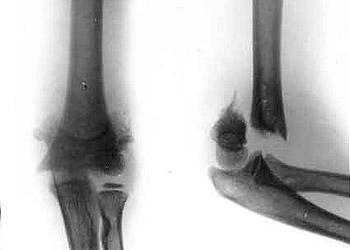

Osteosynthesis of upper arm by means of Veklich's apparatus. Osteosynthesis of upper arm by means of Veklich's apparatus.

Osteosynthesis of upper arm by means of Veklich's apparatus.